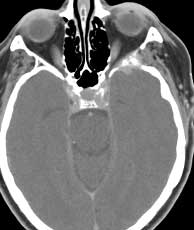

CT post-contrast CT bone windows

Diagnosis: Squamous cell carcinoma

Squamous cell carcinoma of the masticator space often is a consequence of SCCA in the oral cavity which is spread via perineural pathways or by direct extension from the retromolar trigone. In this case; however, the bulk of the lesion was centered in the suprazygomatic masticator space and is believed to originated in the right external auditory canal. At surgery, the tumor was found invading the temporal bone and entering the middle cranial fossa. Other entities which may be considered in the differential include metastasis and less likely osteosarcoma. Chondrosarcoma may be a consideration however these occur at the region of the temporomandibular joint. Ewing sarcoma or rhabdomyosarcoma are considerations in younger patients. Related Cases